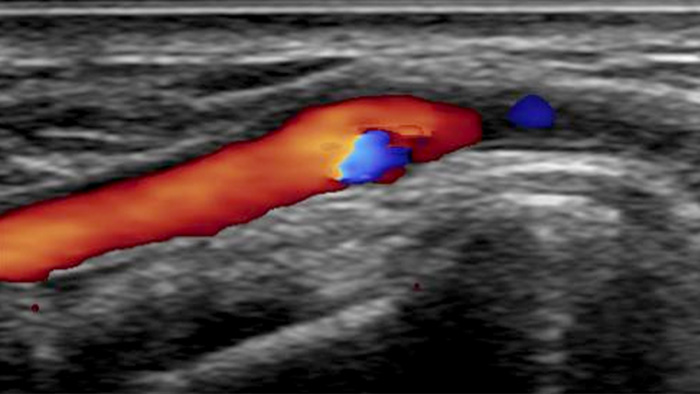

É necessária uma visualização realista do sistema vascular arterial para aceder eficazmente ao sistema arterial. O nosso sistema de ultrassons CX50 integrado fornece imagens de alta qualidade da artéria radial e das veias para suportar intervenções de acesso radial.